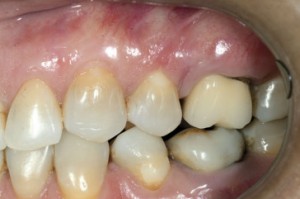

| Pacjentka w wieku 40 lat przed leczeniem. Mnogie (wysokie i szerokie) recesje dziąsła, ryc. 1 | Pacjentka w wieku 40 lat przed leczeniem. Mnogie (wysokie i szerokie) recesje dziąsła, ryc. 2 | |

| Pacjentka w wieku 40 lat przed leczeniem. Mnogie (wysokie i szerokie) recesje dziąsła, ryc. 3 | ||